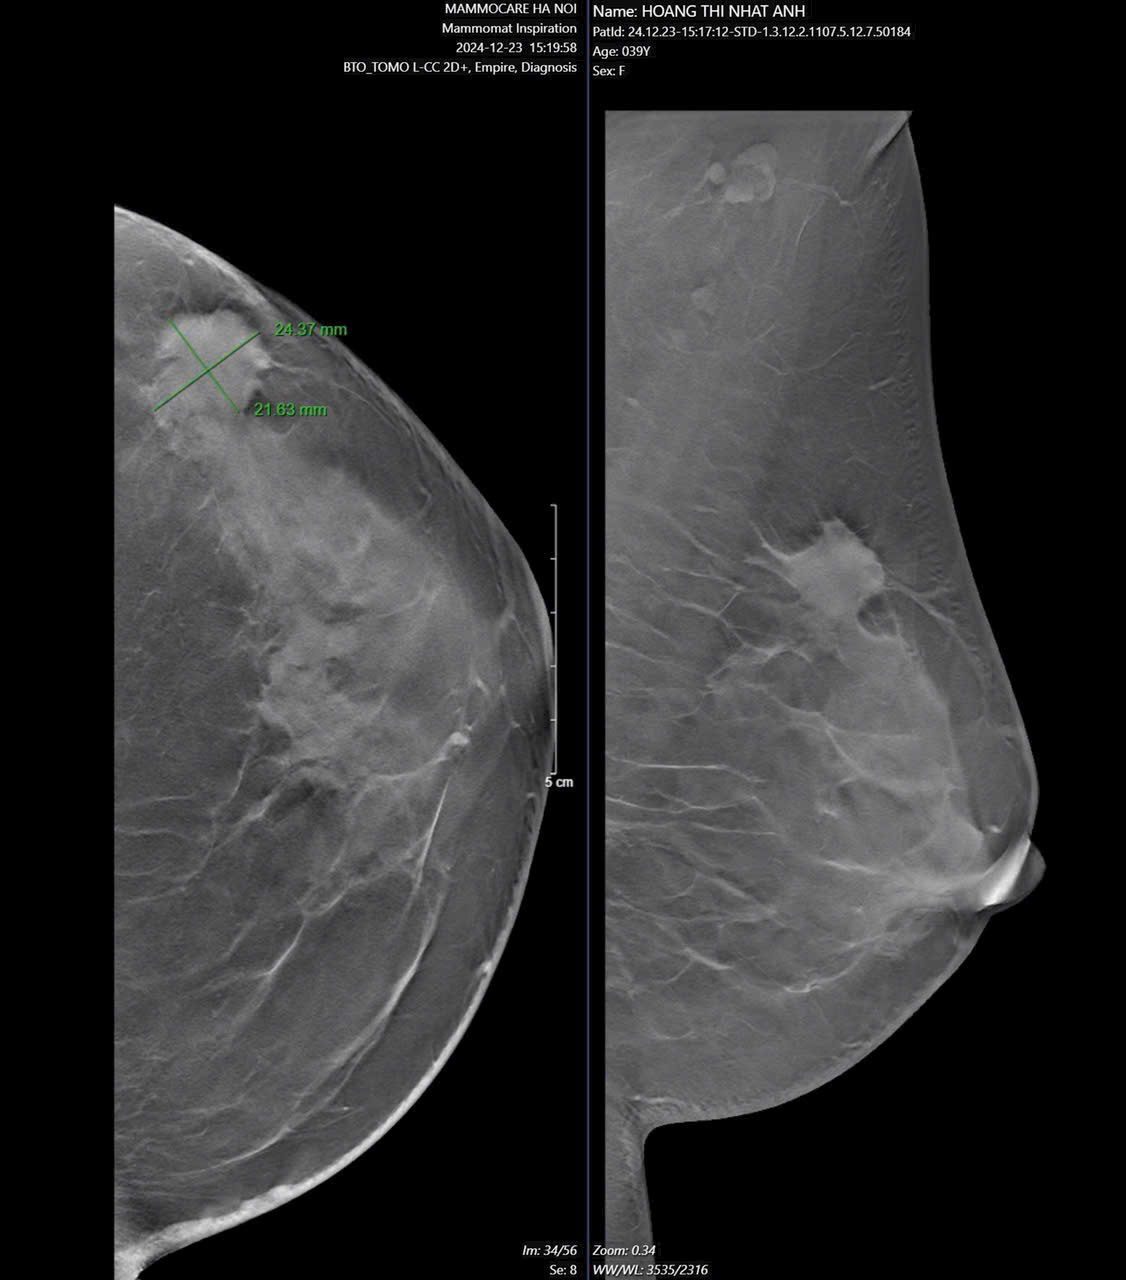

XQUANG VÚ 3D tại Mammocare: Chất Lượng Cao, Công Nghệ Hiện Đại với Máy Mammomat Inspiration

Ung thư vú là một trong những bệnh lý nguy hiểm nhưng hoàn toàn có thể chữa khỏi nếu được phát hiện sớm. Một trong những công cụ tầm soát hiệu...